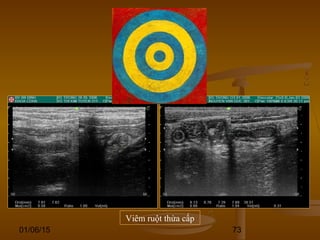

DẤU HIỆU BIA BẮNDẤU HIỆU BIA BẮN

(TARGET SIGN)(TARGET SIGN)

 Hình ảnh những vòng đồng tâm hồi âm dày và hồiHình ảnh những vòng đồng tâm hồi âm dày và hồi

âm kém xen kẽ hoặc là vòng tròn hồi âm kém vớiâm kém xen kẽ hoặc là vòng tròn hồi âm kém với

trung tâm hồi âm dày.trung tâm hồi âm dày.

 Dấu hiệu này có thể thấy ở nhiều bệnh lý của ốngDấu hiệu này có thể thấy ở nhiều bệnh lý của ống

tiêu hóa.tiêu hóa.

 Nó có thể là sự dày lên của vách ống tiêu hóa doNó có thể là sự dày lên của vách ống tiêu hóa do

viêm (VRT, viêm ĐT giả mạc), u, thiếu máu, phìviêm (VRT, viêm ĐT giả mạc), u, thiếu máu, phì

đại (hẹp môn vị phì đại).đại (hẹp môn vị phì đại).

 Hoặc có thể là hình ảnh của các đoạn ống tiêuHoặc có thể là hình ảnh của các đoạn ống tiêu

hóa lồng vào nhau (lồng ruột).hóa lồng vào nhau (lồng ruột).

Viêm ruột thừa cấp